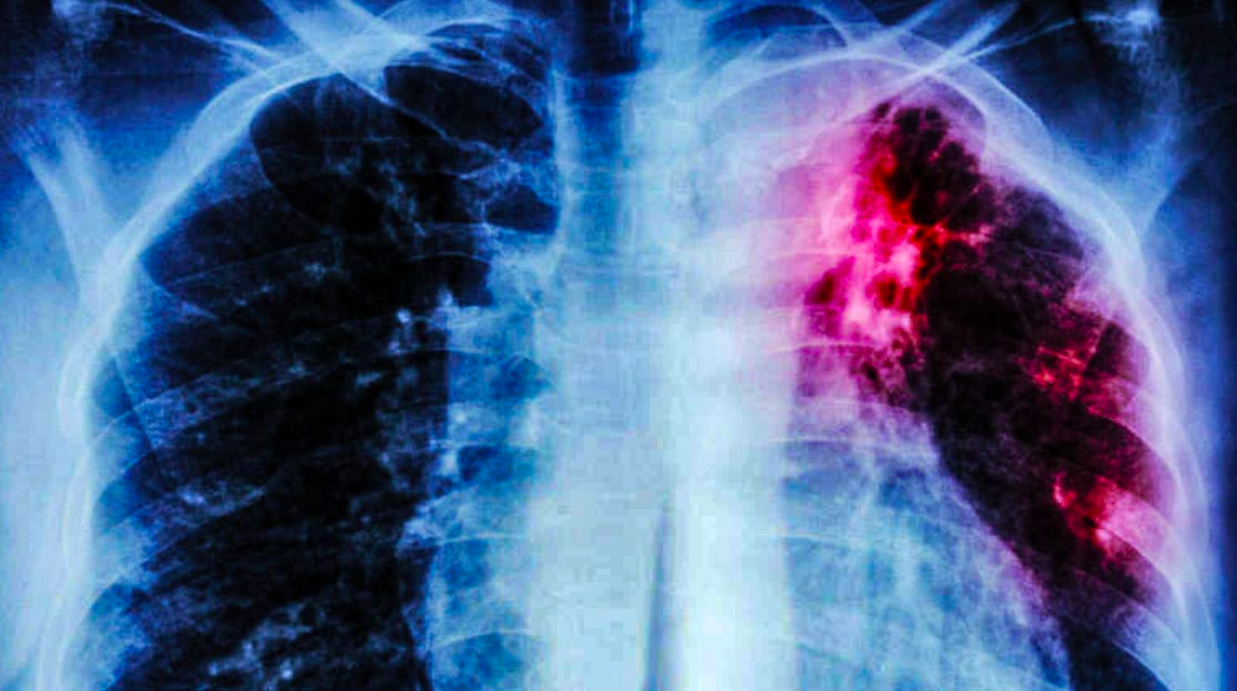

Unos 10 millones de personas enfermaron de tuberculosis en el mundo durante 2017, de las que 1.6 millones fallecieron. El tratamiento actual tiene 40 años y han surgido cepas que muestran resistencia, por lo que urge encontrar nuevas estrategias terapéuticas.